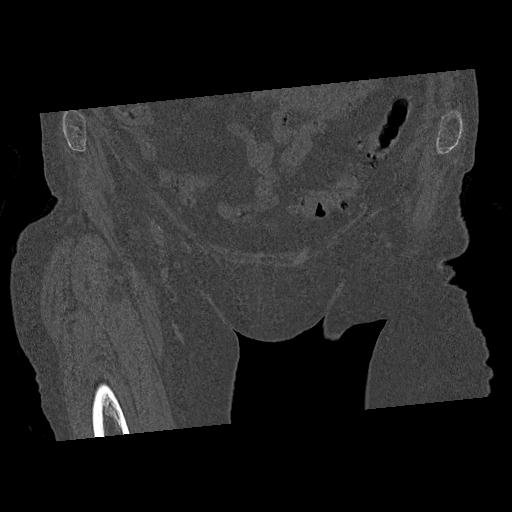

110286 2/17 股関節 2R 74歳女性 右人工骨頭